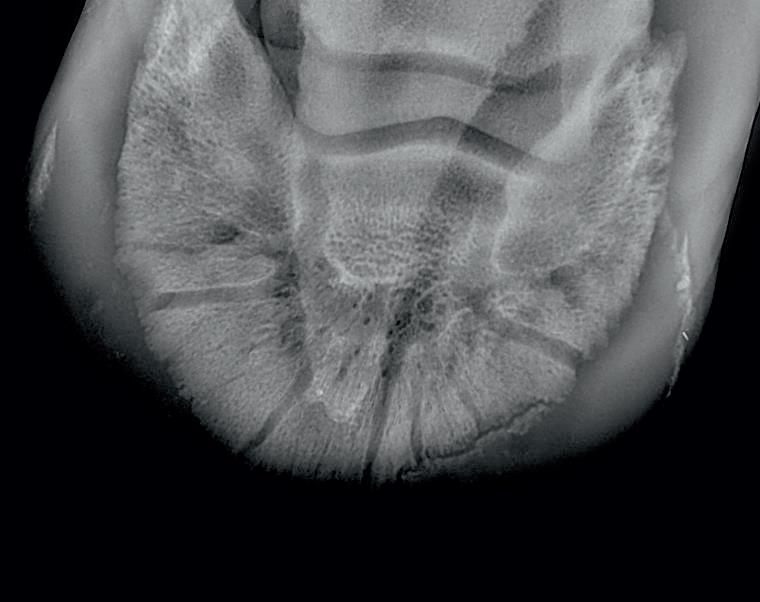

Radiographic proof in clinical results

BONE Gold nutritional bone joint and collagen supplement was formulated to provide some of the essential amino acid requirements of collagen type I, II and III (found in bone and connective tissue) in addition to supporting the nitric oxide pathway which has been found to assist in the formation of bone callus postinjury.

Veterinary surgeons have recommended that Bone Gold may assist with sore shins, tendon injuries, ligament injuries, osteoarthritis and post-surgery in horses and polyarthritis, geriatric osteoarthritis, and post-surgery in dogs.

Here is a veterinary radiographic report on a horse with a fracture evident on the medial toe and after treatment and feeding Bone Gold during this period. More information on these products can be found at www.vetgold.com.au

VETERINARY RADIOGRAPHIC REPORT

HORSE: "XXXXXXXX"

DATES OF EXAMINATION: 26TH AUG, 21ST OCT 21 & 17TH NOV '21

PLACE: XXXXXXXXXX FARM

XXXXXXX's left and right front feet were radiographed on 26th Aug, 21st Oct (8 weeks) and again on the 17th Nov '21(12 weeks).

RADIOGRAPHS:

26.08.21: Right Front: Large P3 solar margin fracture evident on medial toe 32.6mm x 4.1mm with approximately 1.4mm separation from parent bone as below left image.

21.10.21: Right Front: Fine residual 4.2mm fracture still evident, approximately 90% resolution

17.11.21: Right Front: Fracture fully resolved

RECOMMENDATIONS:

Radiographic results as of the 17th Nov '21 show total resolution of the original fracture.

XXXXXXX was reshod today utilising off an alloy shoe with a toe clip - inner circumference seated out to avoid any sole pressure.

The horse can return to training. Please do not hesitate to contact me if you have any further queries

COMMENTS:

Solar margin Type IV fractures of this magnitude have well-documented internationally published healing rates of 7 - 12 months. Full resolution of these fractures is rare as most often the fracture fragments are resorbed.

Full resolution in a 3 month period was not anticipated.

The horse was on Bone Gold 3 x scoops fed once per day for this period.